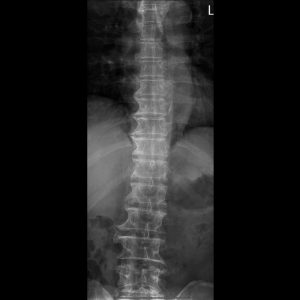

T-spine A-P view

T-spine Lateral view

T-L spine AP view

T-L spine Lateral view